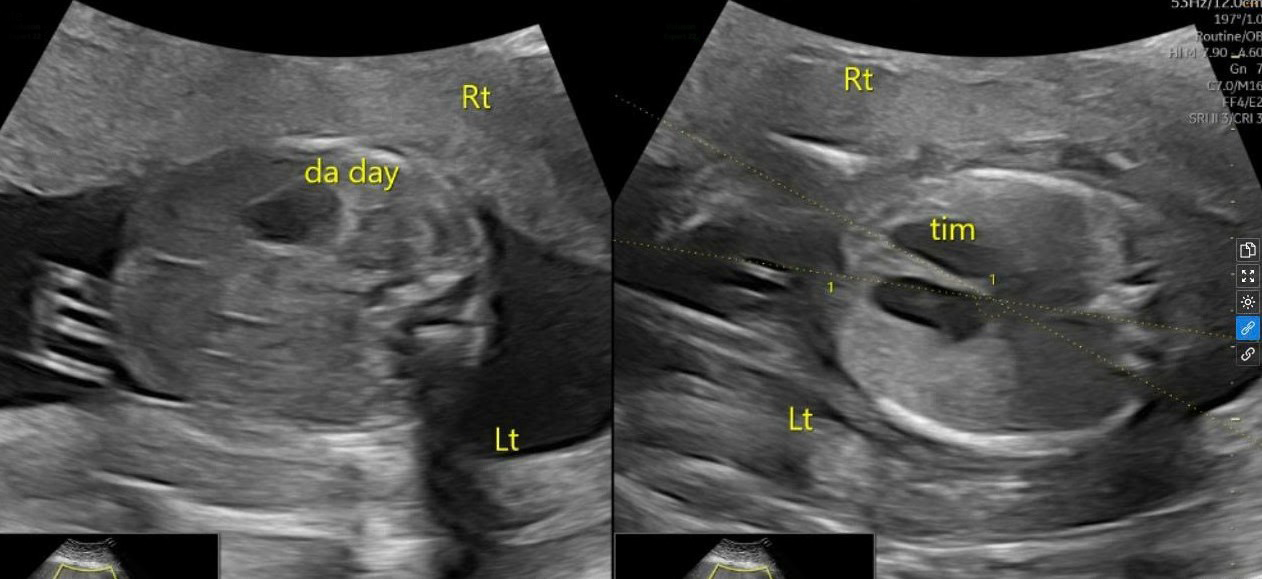

Ultrasound image showing the fetal heart and stomach on the right side. *Photo: Tam Anh General Clinic District 7* |

The 29-year-old mother received first-trimester prenatal care at a local private clinic, where no abnormalities were noted. She screened high risk for pre-eclampsia and was prescribed Aspirin for prevention. At 20 weeks of pregnancy, she visited Tam Anh General Clinic District 7. Doctor Nguyen Thi Lien Phuong, a specialist in fetal medicine, performed an ultrasound that revealed the fetal heart and stomach were on the right side of the body, instead of the usual left, indicating situs inversus. This condition means the body's organs are positioned opposite to their normal anatomical locations.

To determine the cause of the situs inversus, the pregnant woman underwent amniocentesis. Specialized gene sequencing revealed the fetus carried a heterozygous MMP21 gene mutation, an autosomal dominant inheritance pattern, linked to Heterotaxy syndrome. Situs inversus associated with Heterotaxy syndrome often results in abnormal organ arrangement in the chest and abdomen, leading to complex heart defects and other serious complications. However, in this specific case, the ultrasound showed the fetal organs were reversed in a "mirror image" fashion, with no accompanying malformations. Doctor Phuong noted, "This condition currently lacks comprehensive statistics in world medical literature," while offering a positive prognosis that it was unlikely to cause severe health problems for the child.